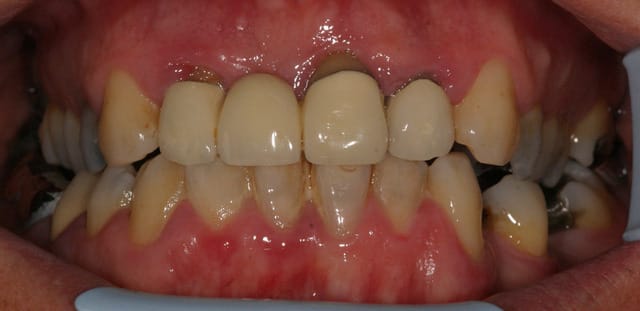

Ca c'est un boulot qui m'a fait extrêmement plaisir, parce que je trouve qu'on touche là à l'essence même de notre activité: permettre aux gens de manger.

Ce monsieur, 80 piges au compteur, est arrivé avec des vieilles provisoires, des gros compos, tout se cassait la figure... "Oh, mais à mon âge est-ce que ça vaut bien le coup de mettre des sous dans les dents..."

Pas de vraies difficultés techniques, pas de recherche esthétique marquée, du métal, on a reconstruit une occlusion de 5 à 5 seulement. Mais niveau qualité de vie, j'aimerai être toujours aussi efficace.

Photos un an après la pose. Pano avant.